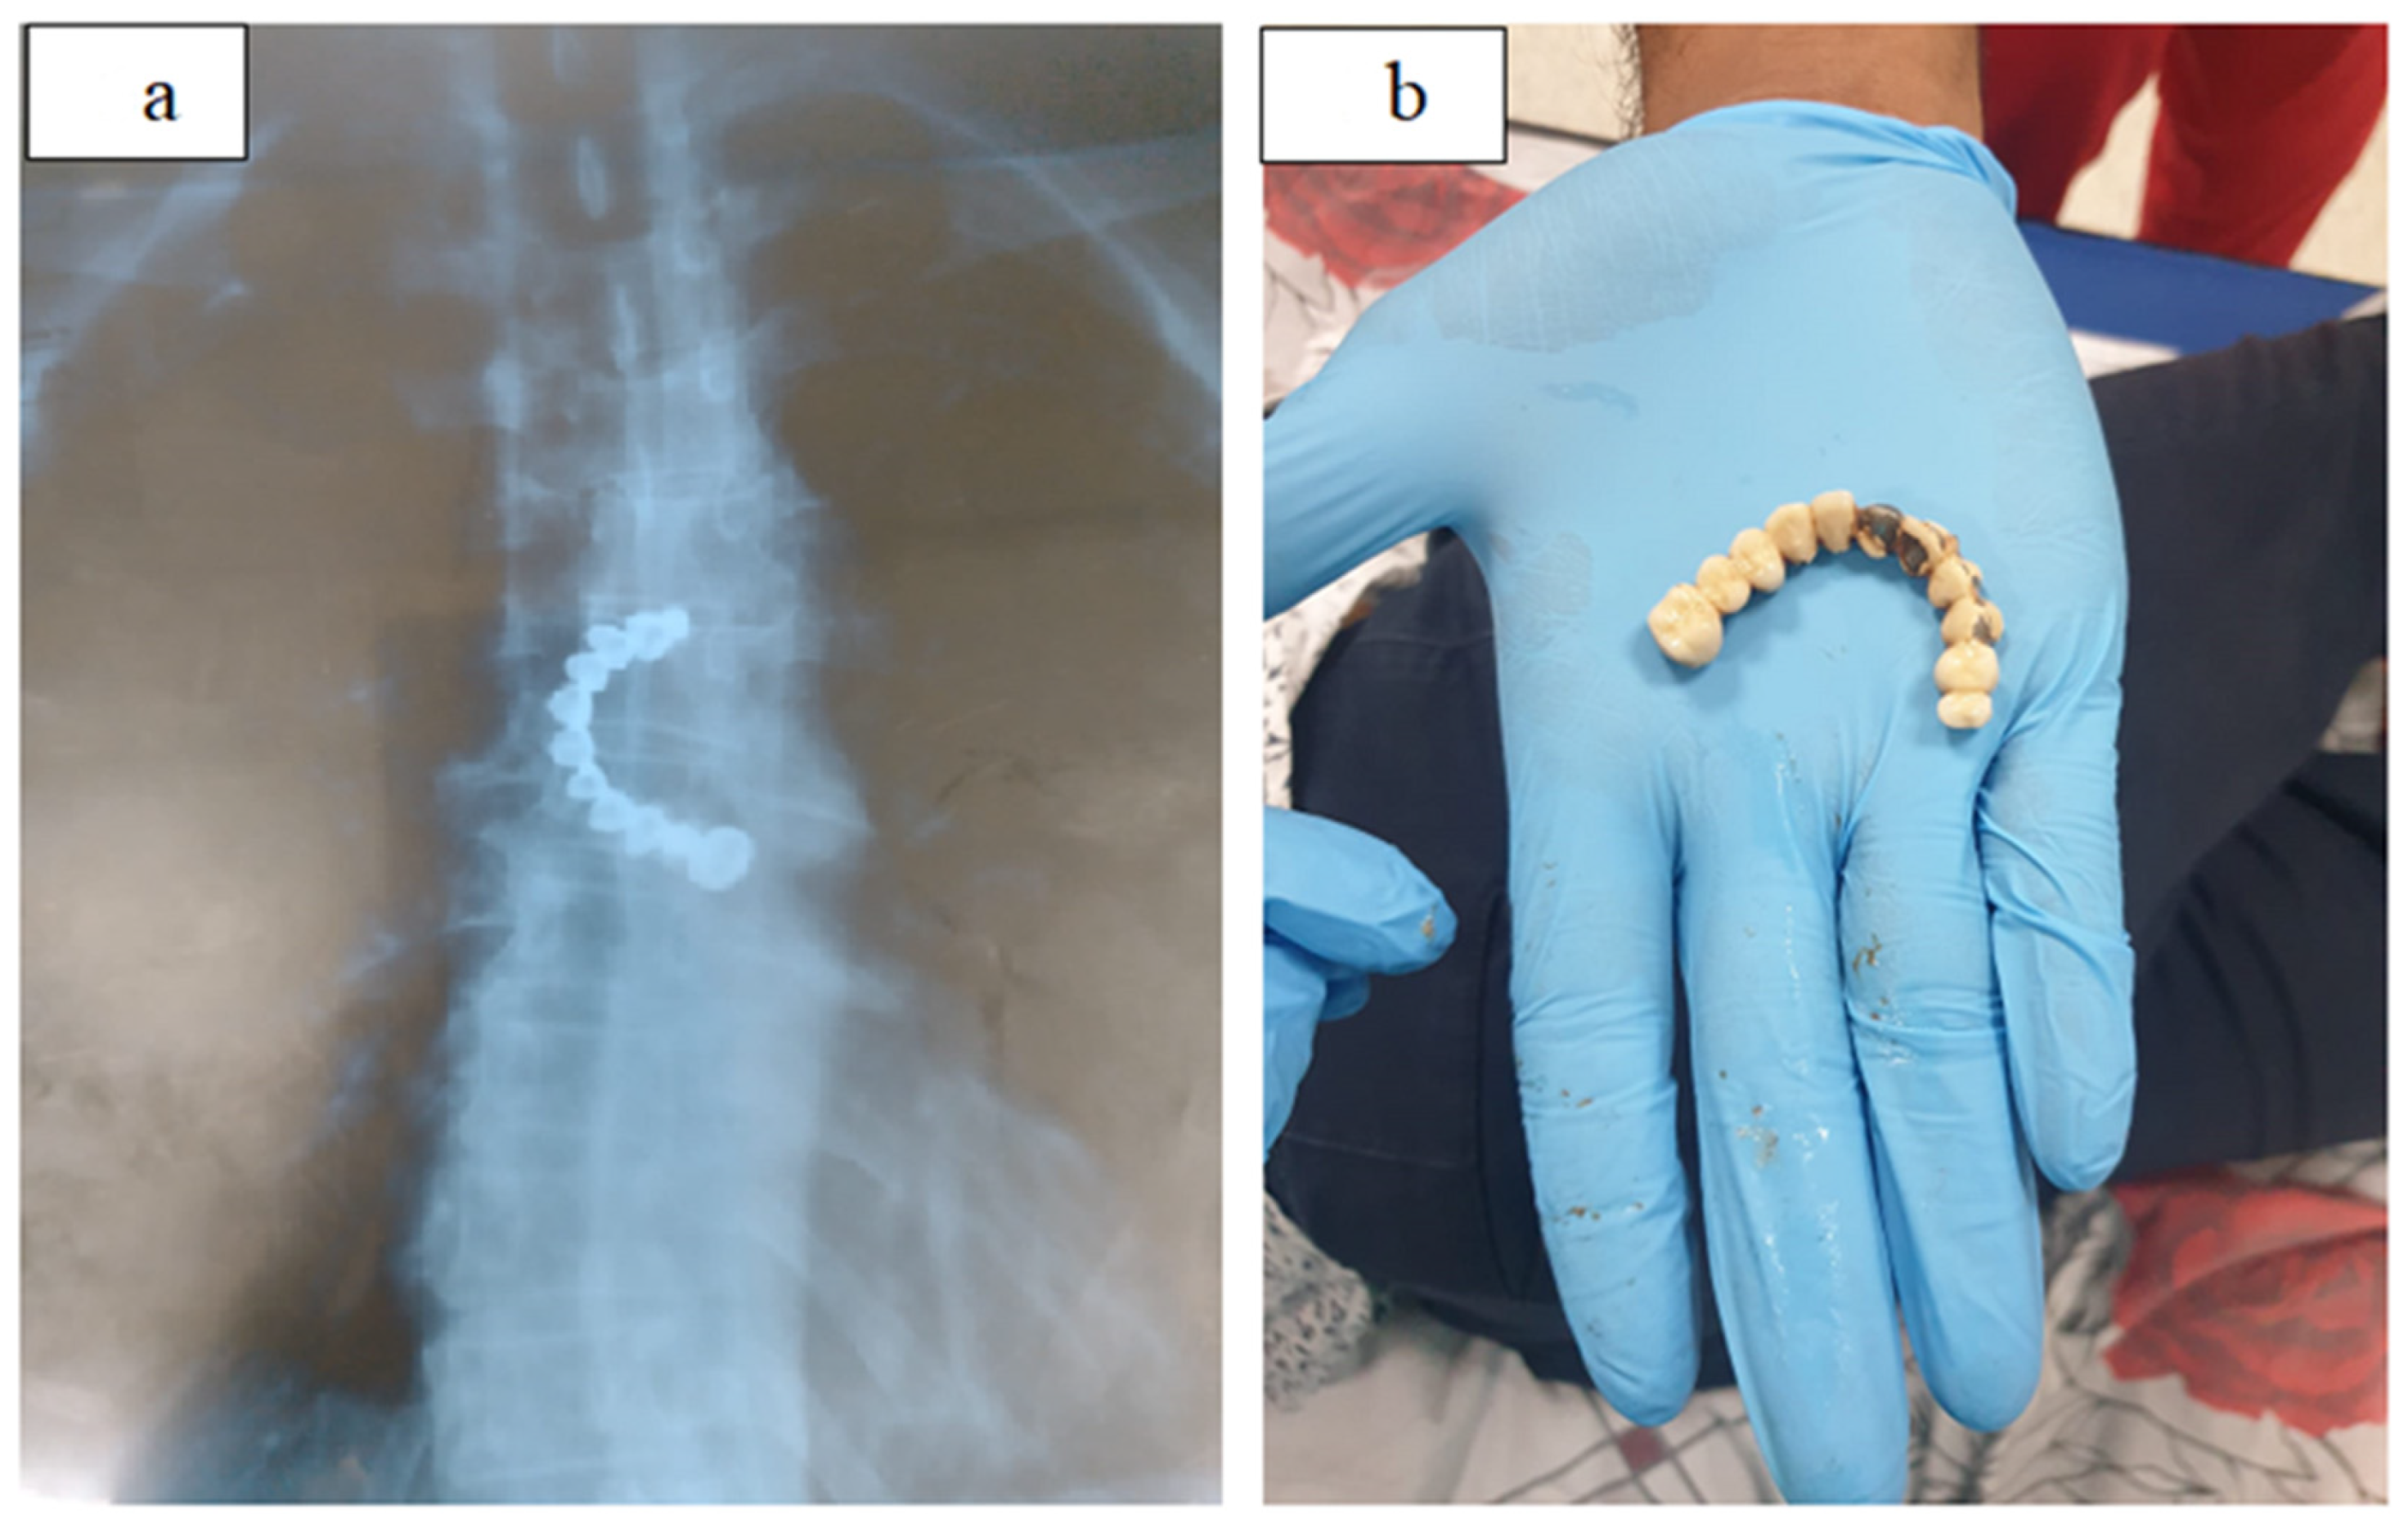

Sharp or pointed foreign bodies must be extracted as a priority before passing through the stomach, as there is a high risk of them perforating the intestine [22]. Swallowing sharp foreign bodies such as bones (Figure 2), toothpicks and dental apparatus or plaque (Figure 3) can be dangerous as they can affect the airway, perforate or penetrate the intestine, form aortic or tracheal fistulas or cause cardiac tamponade [9]. The most common objects that can cause organ perforation are fish or chicken bones, but also toothpicks and plastic cutlery [40]. Fish bones usually remain in the mouth, larynx and pharynx, but also in the upper esophagus [41]. For non-penetrating bones, extraction with alligator clips is easiest. Penetrating bones that cannot be extracted endoscopically are extracted surgically [41]. Swallowed drug blisters can damage the esophagus and can be removed with a recovery net [42].

Figure 3.

(a,b). Dental plaque in esophagus, extraction with polypectomy snares. Emergency Clinical Hospital Bucharest collection.